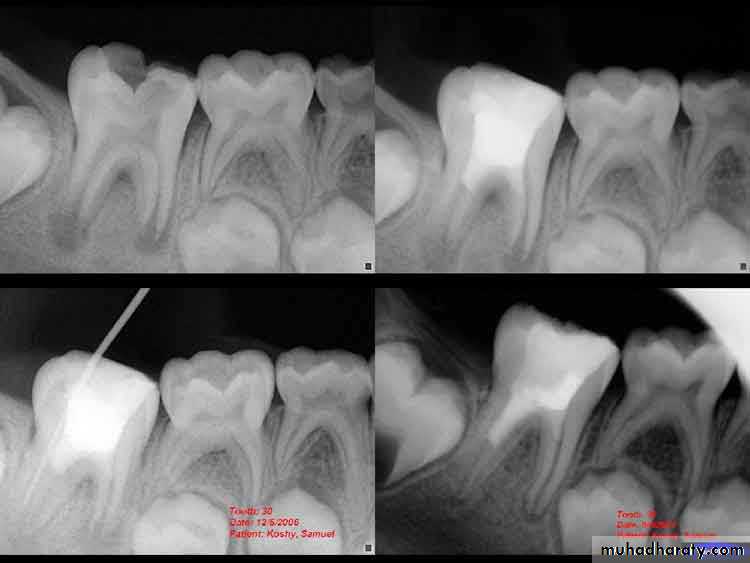

Comparison of dentin bridge formation using mineral trioxide aggregate (MTA) or calcium hydroxide in dog pulps.A,After 1 week, a noticeable bridge has formed subjacent to MTA.B,A comparable bridge under calcium hydroxide after 2 weeks.C,A 4-week specimen with MTA shows excellent bridge formation.D,Consistently, the bridge formation under calcium hydroxide lagged behind MTA; an example of bridge formation under calcium hydroxide after 8 weeks. CH = calcium hydroxide; DB = dentin bridge; MTA = mineral trioxide aggregate.